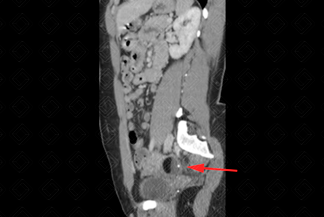

Texto alternativo para a imagem Figuras 1, 2 e 3. Créditos: Dra. Elazir Mota - Rio de Janeiro/RJ.

Descrição das figuras 1, 2 e 3: Tomografia computadorizada do abdome. Estudo pré e pós-contraste (fase portal). Observa-se lesão heterogênea, bem definida, com nível líquido-gorduroso e foco de calcificação ("sinal da pokebola"). A gordura é identificada por uma densidade abaixo negativa (seta vermelha). Essas características de imagem permitem que o diagnóstico de teratoma ovariano maduro possa ser sugerido.

• Tomografia computadorizada do abdome e pelve: O estudo será realizado com contraste venoso idealmente, para melhor caracterização da lesão. A TC, no caso específico do teratoma maduro, possui uma sensibilidade alta para sua caracterização (cerca de 98%). Nela encontram-se áreas com densidade negativa (conteúdo gorduroso), calcificações e, na maioria dos casos, o nódulo mural (Rokitansky) no interior da formação cística. Nesses casos, é possível sugerir o diagnóstico (como nas imagens acima);